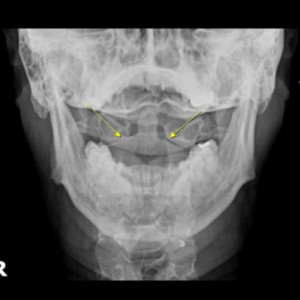

안면 두개골 엑스레이 검사

Submento Vertex View 포함

경추 1,2번의 변위 파악